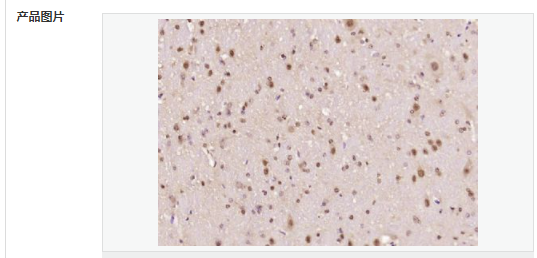

| 产品应用 | ELISA=1:5000-10000 IHC-P=1:100-500 IHC-F=1:100-500 ICC=1:100-500 IF=1:100-500 (石蜡切片需做抗原修复) not yet tested in other applications. optimal dilutions/concentrations should be determined by the end user. |

| 细胞定位 | 细胞核 细胞浆 |

| 产品介绍 | The human ataxin-7 gene, also known as spinocerebellar ataxia 7 or SCA7, maps to chromosome 3p13-p12, has a 2,727-bp open reading frame, and encodes a 892 amino acid protein containing a nuclear localization signal and a polyglutamine tract (1,2). SCA7 is an autosomal dominant neurodegenerative disorder characterized by ataxia and selective neuronal cell loss caused by the expansion of a translated CAG repeat encoding a polyglutamine tract in ataxin-7, which is the SCA7 gene product (3,4). Ataxin-7 is expressed within neurons both affected and unaffected in SCA7 pathology with subcellular localization being variable depending upon the neuronal subtype (5). Polyglutamine expanded in ataxin-7 may carry out its pathogenic effects in the nucleus by altering the matrix-associated nuclear structure and/or by disrupting nucleolar function (6). Function: Ataxin 7 is a protein of unknown function. It may be the human orthologue of the yeast SAGA SGF73 subunit and a subunit of the human TFTC-like transcriptional complexes. Spinocerebellar ataxia 7 (one of a group of hereditary neurodegenrative diseases) is caused by an expanded trinucleotide repeat in the gene encoding ataxin 7. Ataxin 7 is typically located in the cytoplasm and on the nuclear membrane of normal brain neurons. In cells where there is a mutation of the SCA7 gene, ataxin 7 accumulates in intranuclear inclusions and can result in cell death. Subunit: Component of the STAGA transcription coactivator-HAT complex, at least composed of SUPT3H, GCN5L2, TAF5L, TAF6L, SUPT7L, TADA3L, TAD1L, TAF10, TAF12, TRRAP, TAF9 and ATXN7. The STAGA core complex is associated with a subcomplex required for histone deubiquitination composed of ATXN7L3, ENY2 and USP22. Interacts with SORBS1, PSMC1 and CRX. Interacts with TRRAP, GCN5L2 and TAF10. Interacts with alpha tubulin. Subcellular Location: Cytoplasmic (isoform b) and Nuclear (isoform a) Tissue Specificity: Isoform a and isoform b are expressed in CNS, but isoform a is expressed predominantly in the peripherical tissues. Isoform b is also highly expressed in the frontal lobe, skeletal muscle and spinal cord and is expressed at a lower level in the lung, lymphoblast and intestine. Post-translational modifications: Proteolytically cleaved. The cleavage may be involved in SCA7 degeneration: the isoform fragments may exert distinct toxic influences that could contribute to selective neurodegeneration. Sumoylation decreases the aggregation propensity and cellular toxicity of forms with an expanded poly-Gln region but has no effect on subcellular location or interaction with components of the STAGA complex. DISEASE: Defects in ATXN7 are the cause of spinocerebellar ataxia type 7 (SCA7) [MIM:164500]; also known as olivopontocerebellar atrophy III (OPCA III or OPCA3) or olivopontocerebellar atrophy with retinal degeneration. Spinocerebellar ataxia is a clinically and genetically heterogeneous group of cerebellar disorders. Patients show progressive incoordination of gait and often poor coordination of hands, speech and eye movements, due to degeneration of the cerebellum with variable involvement of the brainstem and spinal cord. SCA7 belongs to the autosomal dominant cerebellar ataxias type II (ADCA II) which are characterized by cerebellar ataxia with retinal degeneration and pigmentary macular dystrophy. Similarity: Belongs to the ataxin-7 family. Contains 1 SCA7 domain. SWISS: O15265 Gene ID: 6314 Database links: Entrez Gene: 6314 Human Entrez Gene: 246103 Mouse Omim: 164500 Human Omim: 607640 Human SwissProt: O15265 Human SwissProt: Q8R4I1 Mouse Unigene: 476595 Human Important Note: This product as supplied is intended for research use only, not for use in human, therapeutic or diagnostic applications. |